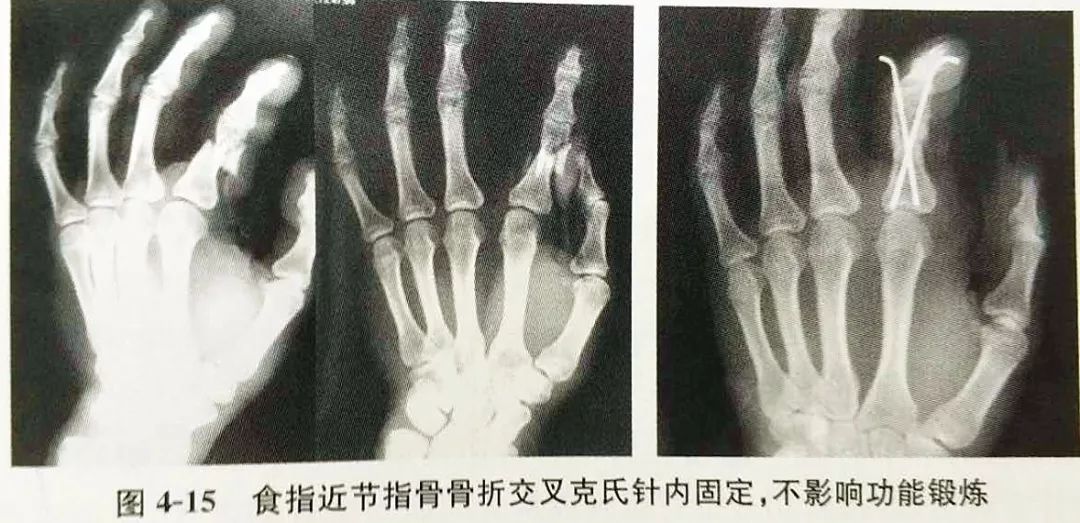

關於近中節指骨骨折 你想知道的 這裡都有答案 每日頭條

掌指骨骨折的固定方式选择 你都清楚吗 医学界 助力医生临床决策和职业成长